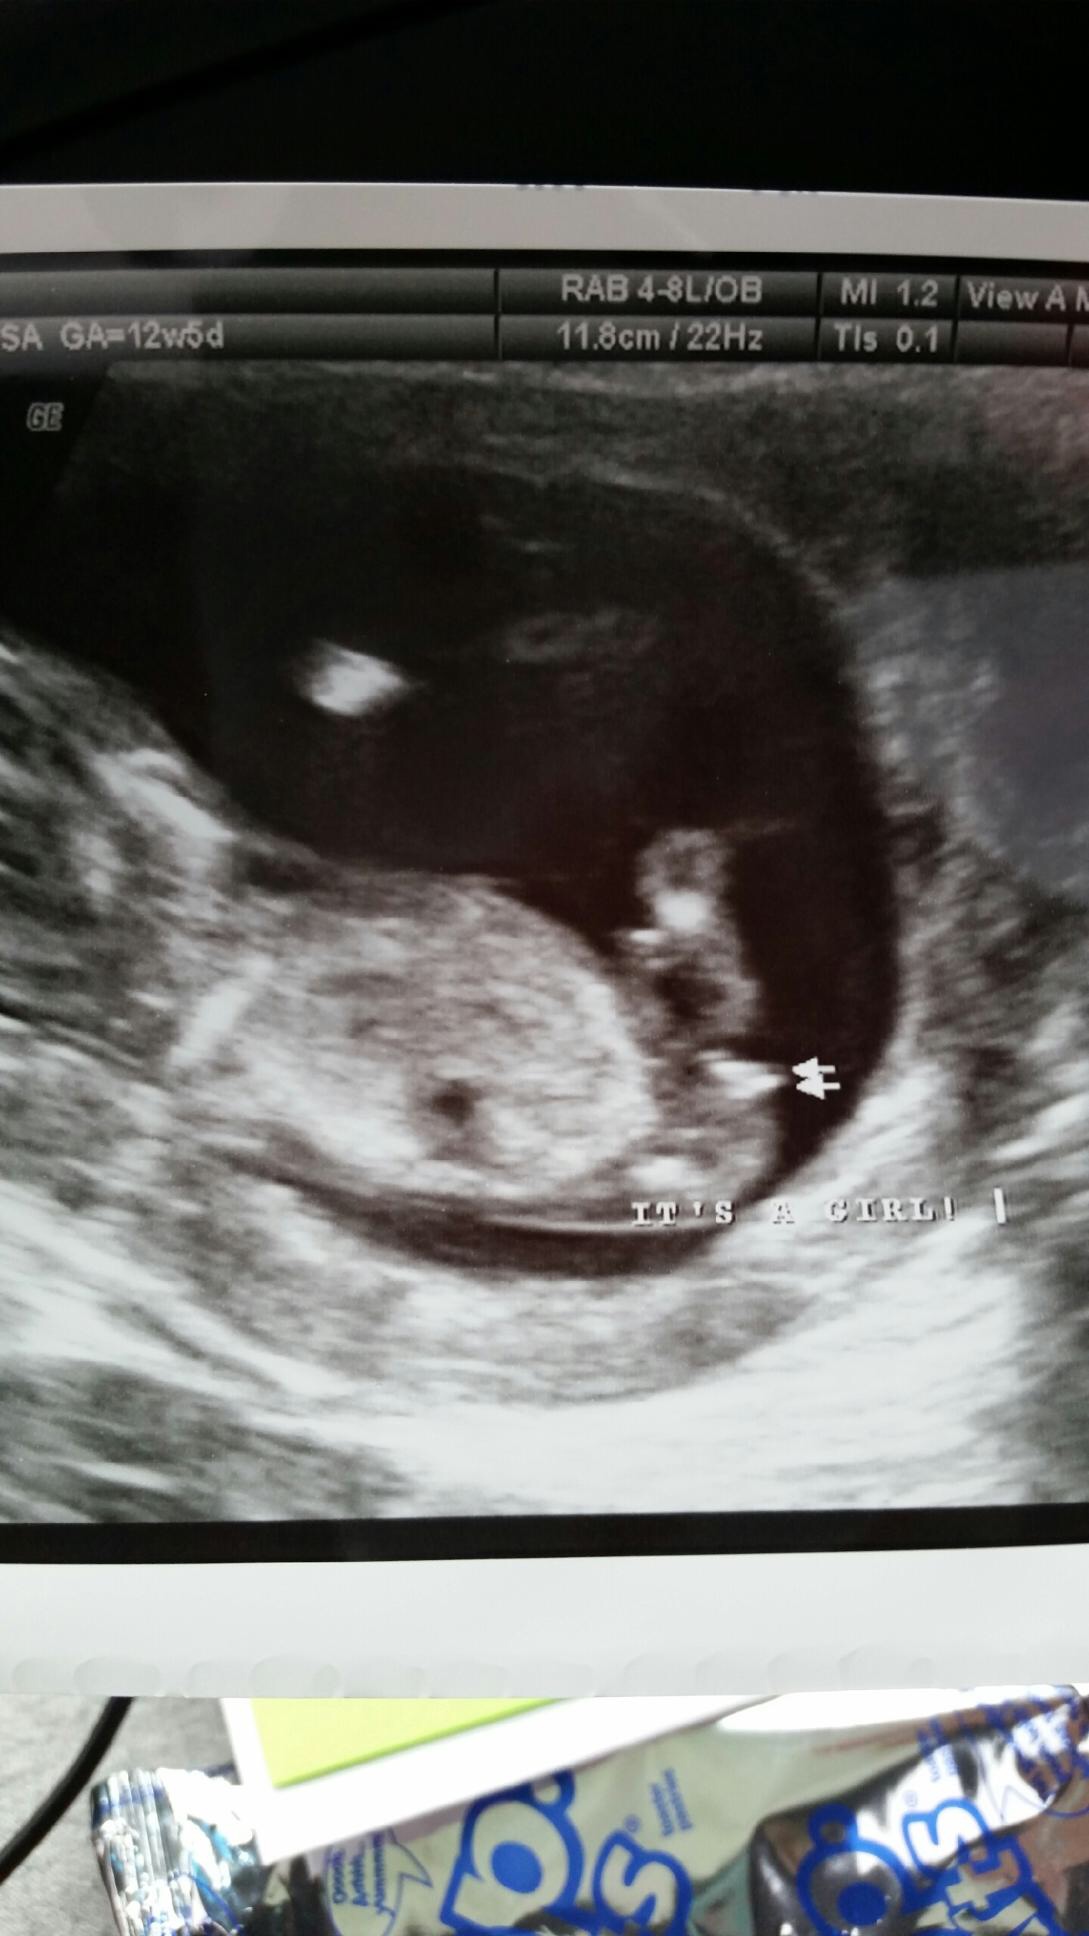

12 weeks 3 days. Tech told me girl and I'm over the moon but I think the potty shot looks like a boy... Opinions please!!!!

I'd really, really, really take that with a grain of salt. 12+3 is really too early to guess on anything but a nub. And even nubs at that stage are not really as accurate as you are looking for. I'd try to keep in mind that it still might be a boy. Not because I think the tech is necessarily wrong, but I think it's a tad irresponsible of a tech (even a trained one) to guess so definitively that early.

Hmmm. Honestly from these I'd say boy. It's still early though.